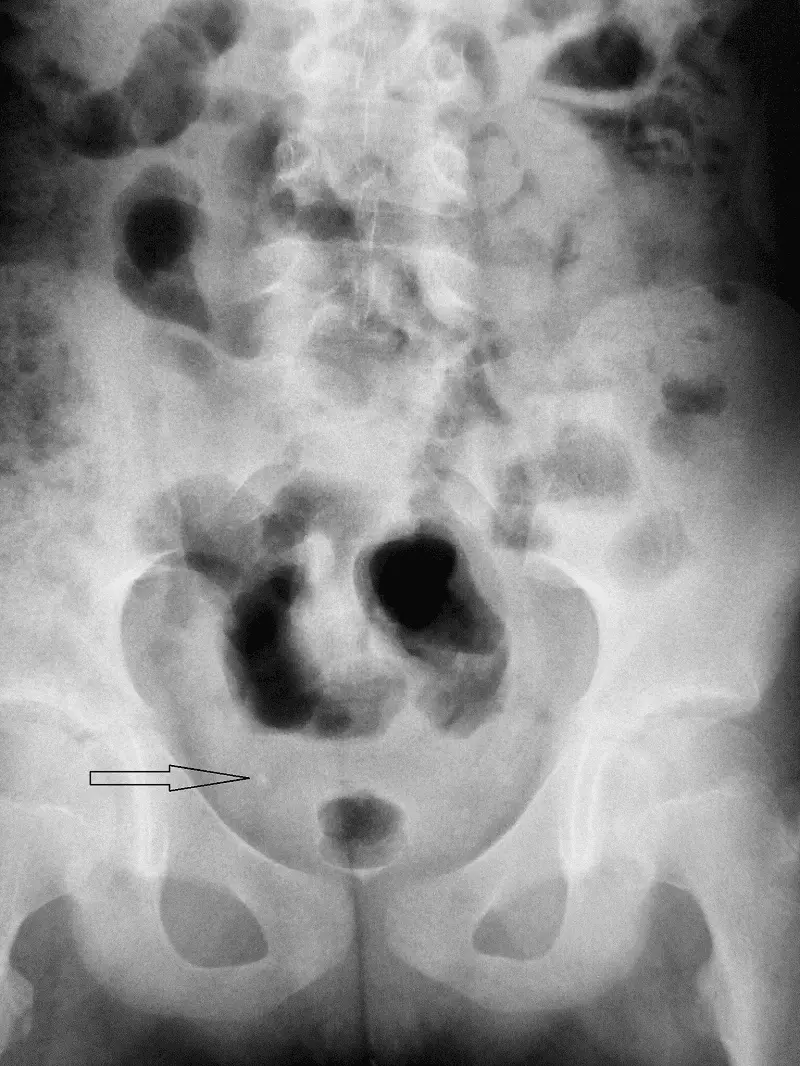

W badaniu tym uwidoczniono prawidłowy pęcherz, z możliwością występowania złogu cieniującego w rzucie moczowodu prawego. Zdjęcie RTG wykonane w trakcie cystografii z widocznym złogiem przedstawiono na rycinie 6.

Ryc. 6. Badanie cystografii mikcyjnej, faza po mikcji – widoczny złóg w rzucie prawego moczowodu